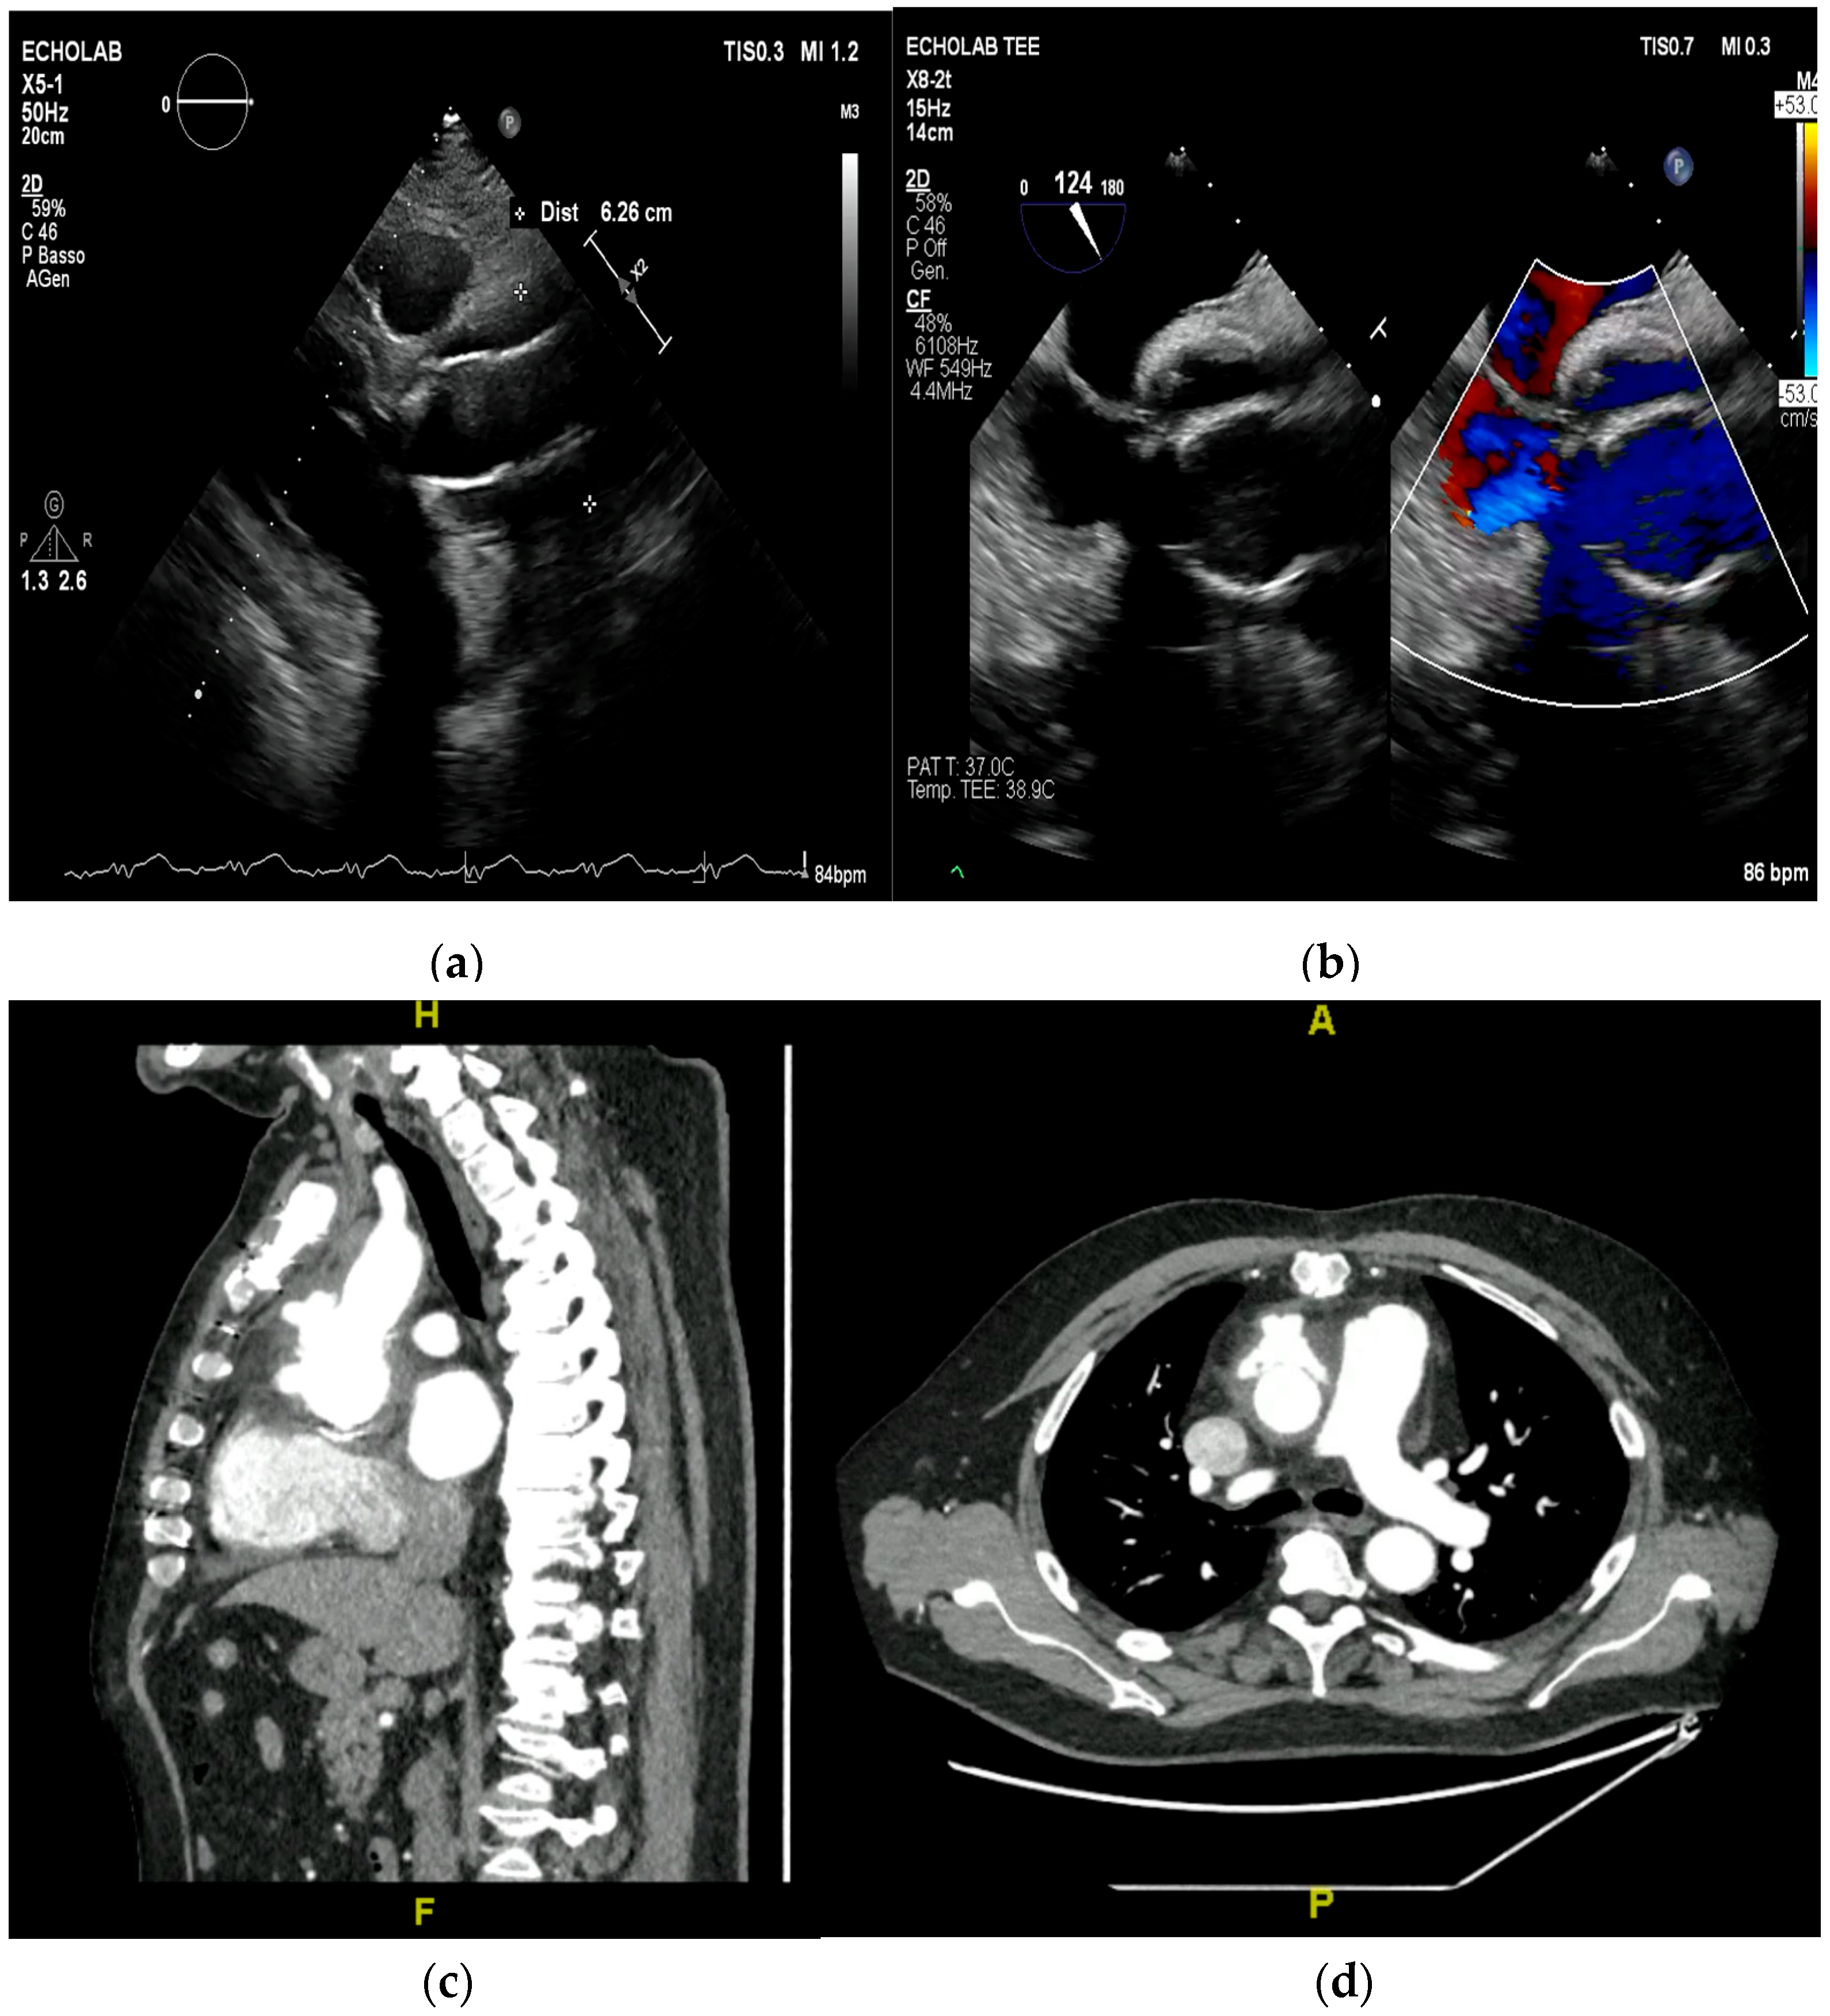

4. Echocardiography

- perivalvular or perigraft abscess, an echolucent or echodense area adjacent to the valve annulus or prosthetic ring often with irregular borders and sometimes with evidence of cavity formation.

- pseudoaneurysm, a contrast-filled outpouching with a narrow neck communicating with the cardiac lumen, often adjacent to the valve annulus. On echocardiography, it appears as a pulsatile cavity with systolic expansion and diastolic collapse.

- intracardiac fistula, visualized as an abnormal communication between cardiac chambers or vessels, is often detected by using color Doppler.

- significant new valvular regurgitation compared with previous imaging, i.e., increase in regurgitant jet size, vena contracta width…

5. Cardiac Computed Tomography